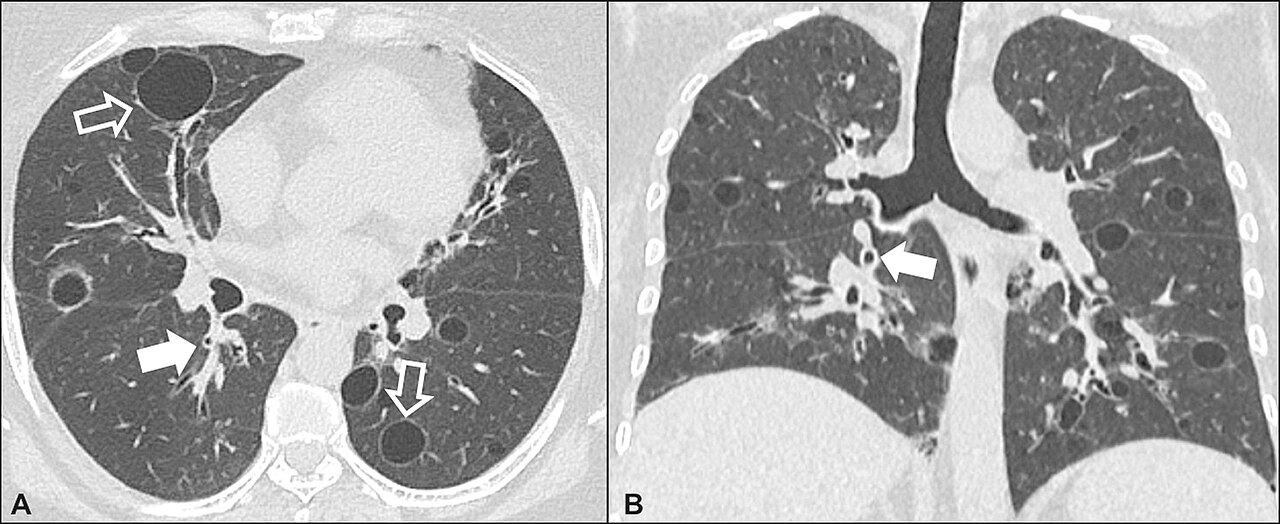

CT — Lung Nodule with Vascular Convergence

CT showing lung nodule with converging pulmonary vessels, a sign suggesting malignancy

CT Downloaded 2026-03-15

Ct

Lung Window 120 kVp W:1500 L:-600

Wikimedia Commons: CT of lung nodule with vascular convergence.png